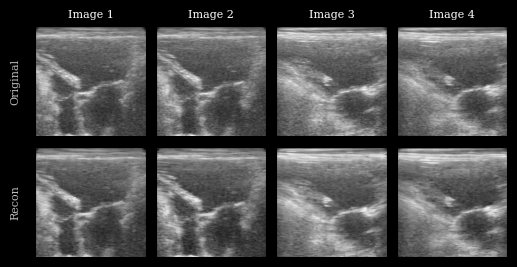

Visualization

We plot the original images and reconstructions for comparison.

../../_images/notebooks_models_taesd_autoencoder_example_15_0.png